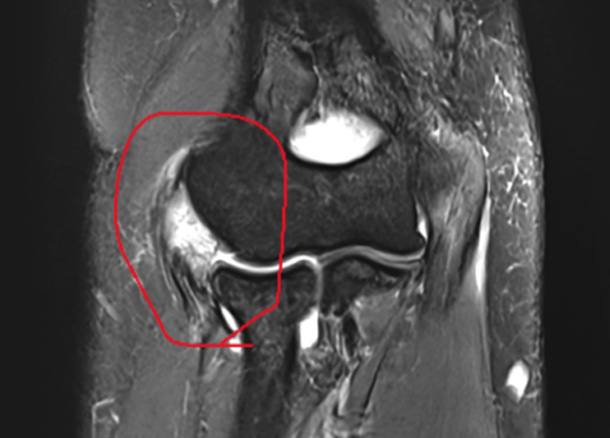

X-Ray, 초음파, MRI 등 검사

신경조직 압박, 신경증상 등 파악

진단 증상에 따라 치료계획을 세웁니다.

Before 수술 전

1년 후 완전 정상화